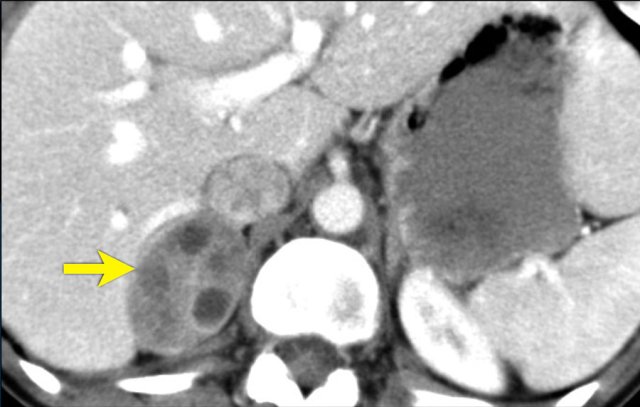

The image shows a heterogeneous ill-defined mass larger than 4 cm.

There is a hypo-enhancing center, which is probably the result of central necrosis.

In this particular case a biopsy was performed and revealed an adenocarcinoma, probably from primary lung carcinoma.

Surprisingly, extensive imaging analysis, including FDG PET-CT, did not detect a primary tumor, however.